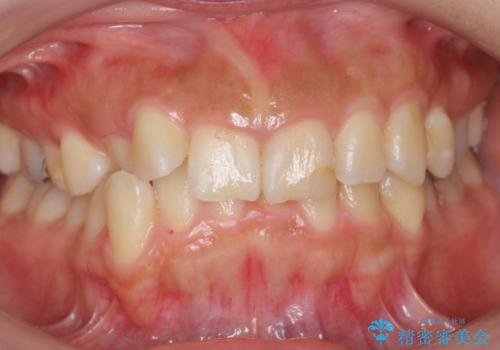

30代女性 前歯のがたつき